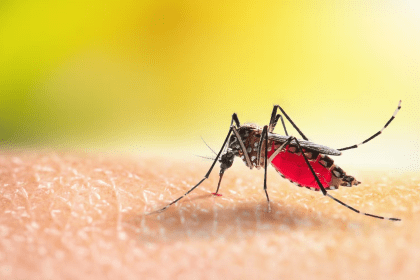

Paludisme au Mozambique : 270 décès enregistrés en cinq mois (autorités)

Au moins 270 personnes sont décédées du paludisme entre janvier et mai…